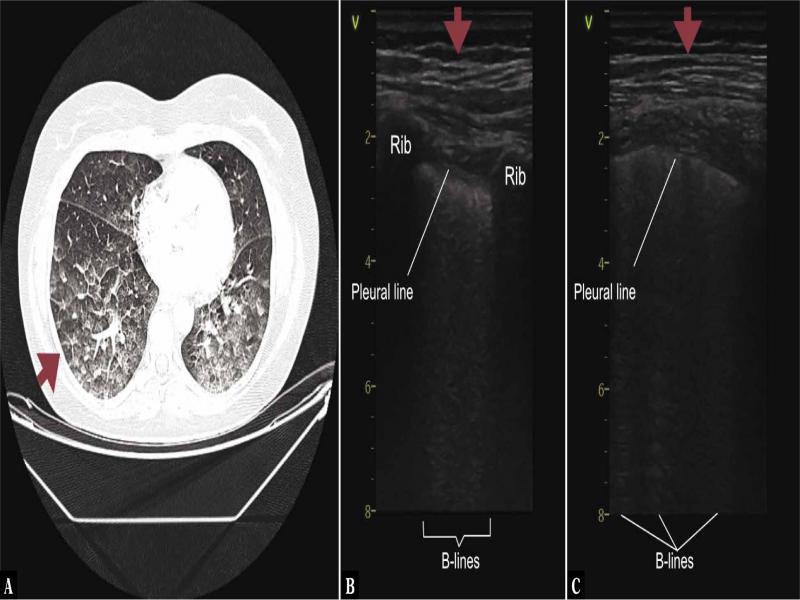

Fig. 1.